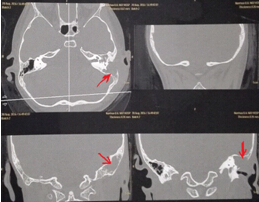

該患兒既往無中耳炎及耳流膿病史,僅表現(xiàn)為1個(gè)月前耳后稍有紅腫、疼痛,在當(dāng)?shù)蒯t(yī)院曾被診斷為“蚊蟲咬傷”所致,家長(zhǎng)也未引起足夠的重視。近半月來,患兒耳后紅腫疼痛加重,遂到我市某三甲醫(yī)院就診,行高分辨率中耳乳突CT,發(fā)現(xiàn)側(cè)顱底、中耳乳突腔巨大新生物占位,乳突骨皮質(zhì)破壞吸收,并可疑耳后骨膜下膿腫形成。病情若進(jìn)一步發(fā)展,膽脂瘤破壞顱底骨質(zhì),將極有可能并發(fā)腦膜炎、腦膿腫,甚至出現(xiàn)敗血癥、腦疝等,危及生命。

3.術(shù)前CT2 4.術(shù)中術(shù)腔中的巨大膽脂瘤